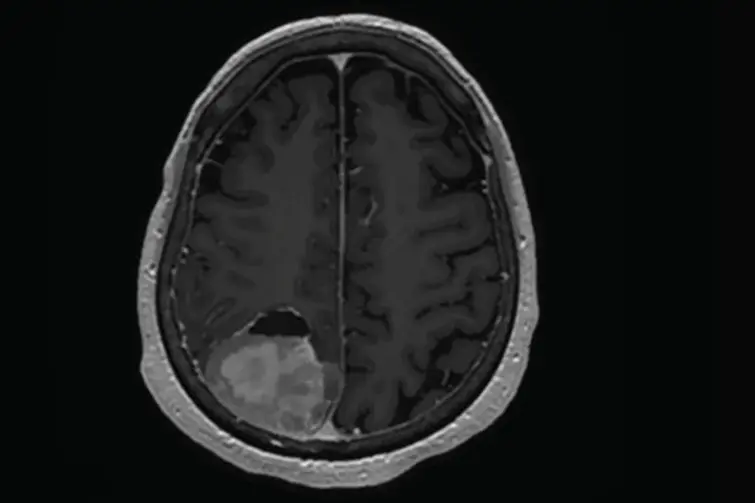

تصویربرداری پزشکی (Medical Imaging)

اولین و مهمترین ابزار برای تشخیص تومور، روشهای تصویربرداری پیشرفته هستند. امآرآی (MRI) و سیتی اسکن (CT Scan) به پزشک اجازه میدهند تا تصویری دقیق از ساختار داخلی بدن به دست آورد. بهویژه در موارد مشکوک به تومور مغزی، MRI با جزئیات بالا میتواند اطلاعات کاملی از محل، اندازه و تاثیر توده بر بافتهای اطراف ارائه دهد و به جراح در برنامهریزی کمک کند.